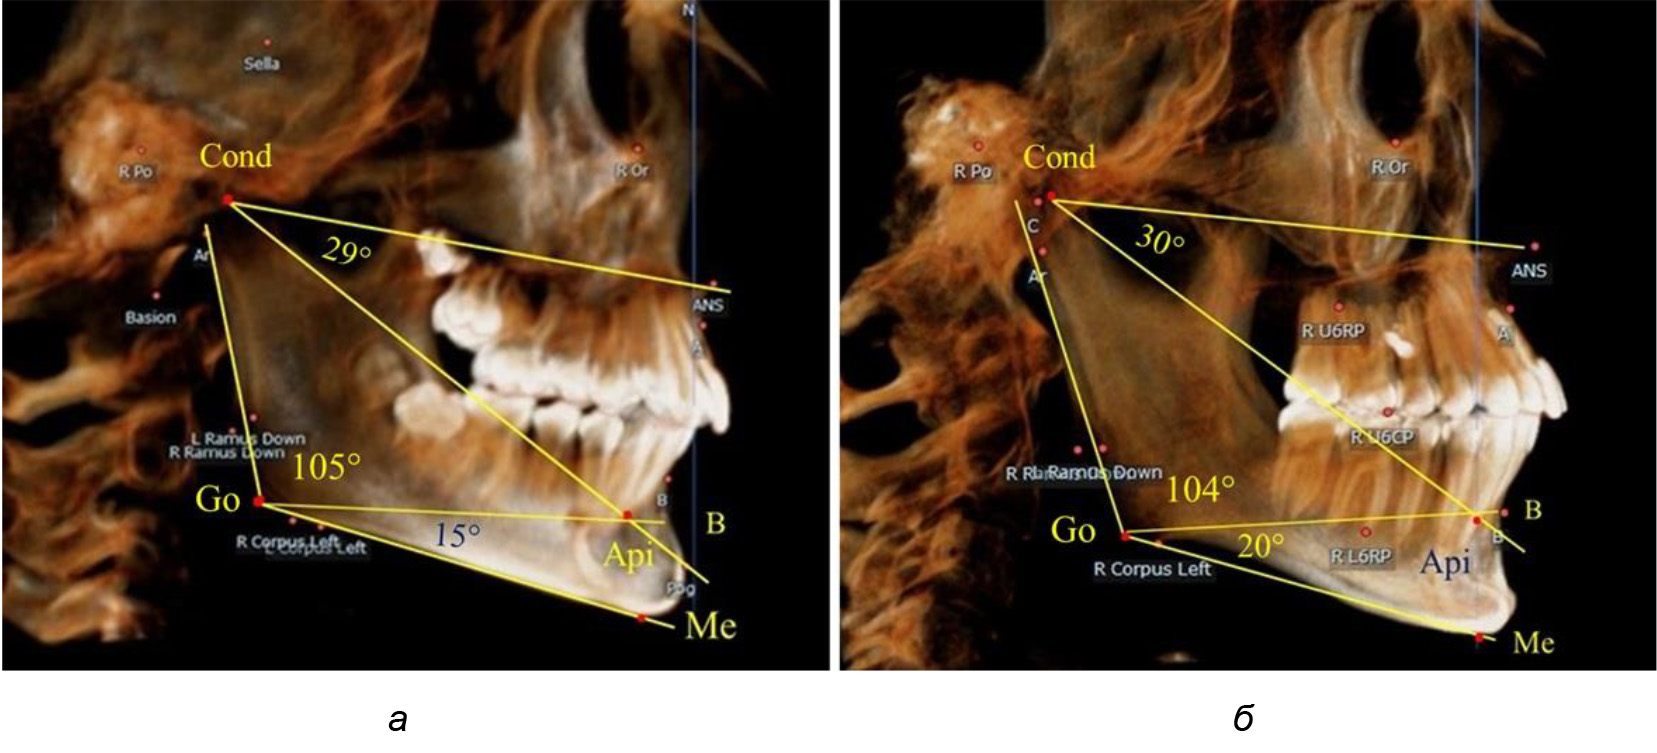

После смены всех молочных зубов (анализ 9 ТРГ) и после прорезывания вторых постоянных моляров (7 человек) происходил очередной этап подъема высоты прикуса с увеличением размеров костей гнатической части лица. Однако величина основного угла гнатической части лица SNA-Cond-Api, так же как в молочном и сменном прикусе, в норме составляла (30,02 ± 1,25)°, что не имело достоверных различий (р ˃ 0,05) с аналогичным параметром, анализируемом в других группах исследования. Угол нижней челюсти и его составляющие отличались вариабельностью параметров при различных показателях нижнечелюстного угла (рис. 6).

Рис. 6. Варианты 3D рентгенограмм детей после смены всех молочных зубов (а) и после прорезывания вторых моляров (б)

Таким образом, данные, полученные при исследовании детей с физиологическим прикусом в различные периоды онтогенеза, показали, что величина основного угла гнатической части лица SNA-Cond-Api была относительно стабильным параметром, вне зависимости от линейных параметров челюстных костей. Данный показатель может служить ориентиром для дифференциальной диагностики зубоальвеолярных и гнатических форм аномалий окклюзии в вертикальном направлении.

При анализе 16 рентгенограмм с аномалиями окклюзии в вертикальном направлении были выявлены признаки изменения основного гнатического угла. Так, для гнатических аномалий глубокой резцовой окклюзии/дизокклюзии (9 человек) отмечалось уменьшение угла гнатической части лица, величина которого была менее 26°. В то же время для гнатических аномалий (7 человек) вертикальной резцовой дизокклюзии («открытый» прикус) определялось увеличение угла гнатической части лица, который превышал значения в 33° (рис. 7).

Рис. 7. Варианты ТРГ при глубоком прикусе (а) и при открытом прикусе (б)

На представленных клинических примерах, несмотря на различия параметров основного угла гнатической части лица, определялись однотипные варианты угла нижней челюсти Ar-Go-Me и его составных частей Ar-Go-Api и Api-Go-Me.